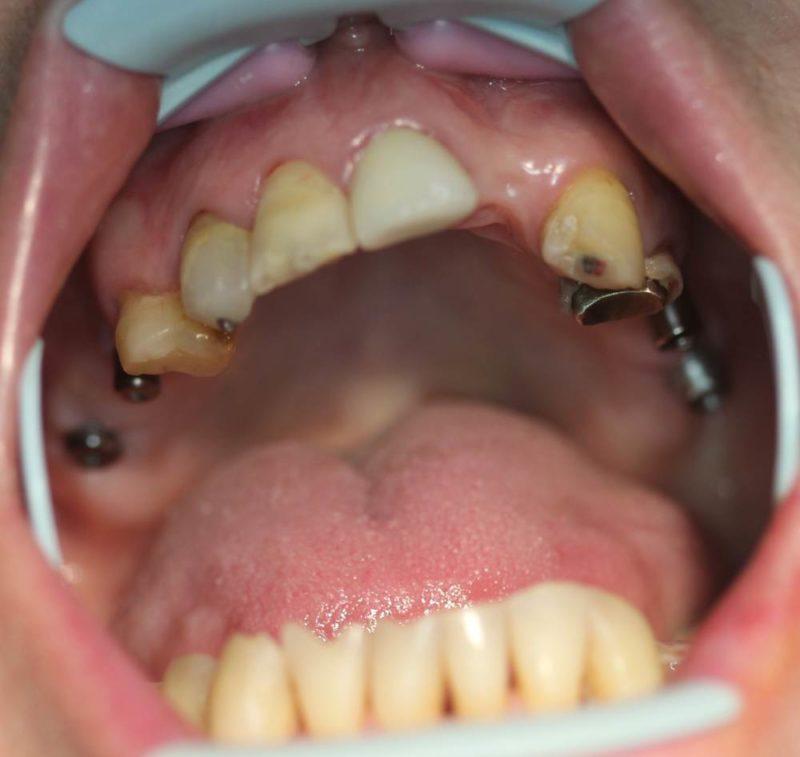

Фото зубов до и после установки имплантатов Nobel